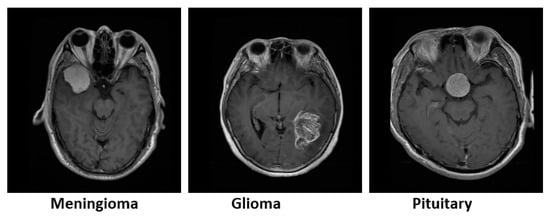

4.1. Dataset